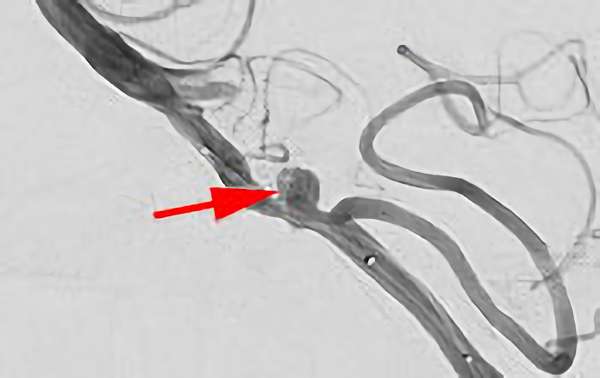

No.1628 手術後